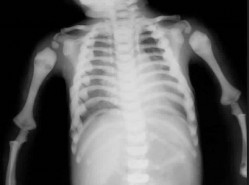

PREFERRED RESPONSE 3 Improved medical management has changed musculoskeletal outcomes for individuals with he…